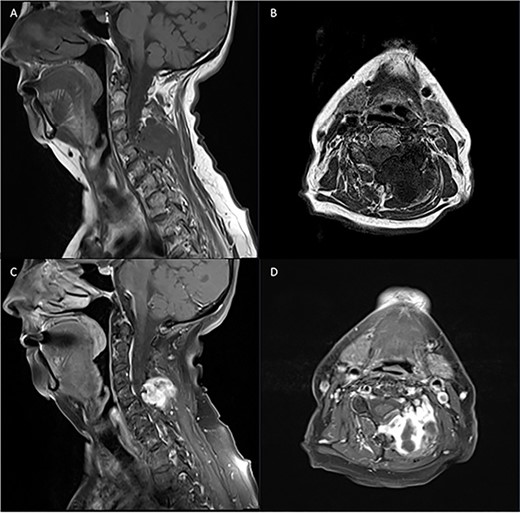

Pre-operative T1 post Gadolinium and T2 weighted MRI: left-sided extra-axial mass at C5/6 with heterogenous enhancement on T1 and hyperintense on T2. Moderate compression of the spinal cord and invasion into surrounding soft tissue.

Diagnostic spinal imaging showed a large mixed cystic solid destructive bony lesion arising from the bony elements at C5 with heterogenous enhancement (Fig. 3). A chest/abdomen/pelvic CT did not identify any further lesions.